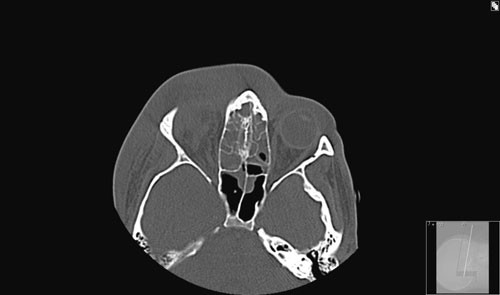

Ny operasjon ble gjennomført, nå sammen med øyelege (fig 4). Conjunctiva ble løsnet medialt mot bulbus og man gikk stumpt bakover til man traff på abscessen mellom mediale rectusmuskulatur og nervus opticus (fig 5). Vi gikk deretter inn i de to foregående abscesshulene, skylte godt og la inn to nye bølgedren. Denne gang normaliserte infeksjonsprøvene seg umiddelbart, og kliniske symptomer gikk raskt i regress. Kontroll-CT med kontrast to dager postoperativt viste nå ingen tegn til abscess. Bakterieundersøkelse med resistensbestemmelse av den første abscessen viste oppvekst av Streptococcus anginosus (Milleri), en abscessogen mikrobesom var sensitiv for penicillin G, og vekst av Fusobacterium necroforum (anaerob),som var sensitiv for metronidazol. Ciprofloksacin ble seponert. Alle dren ble fjernet to dager etter siste operasjon. Synet normaliserte seg, proptosen gikk tilbake og konjunktival blandingsinjeksjon ble behandlet med kloramfenikol salve i en uke. Han ble utskrevet, og videre kontroller skjedde på pasientens lokalsykehus. Ved telefonisk kontakt med pasienten ett år senere hadde han ingen sekveler etter sykdomsforløpet.